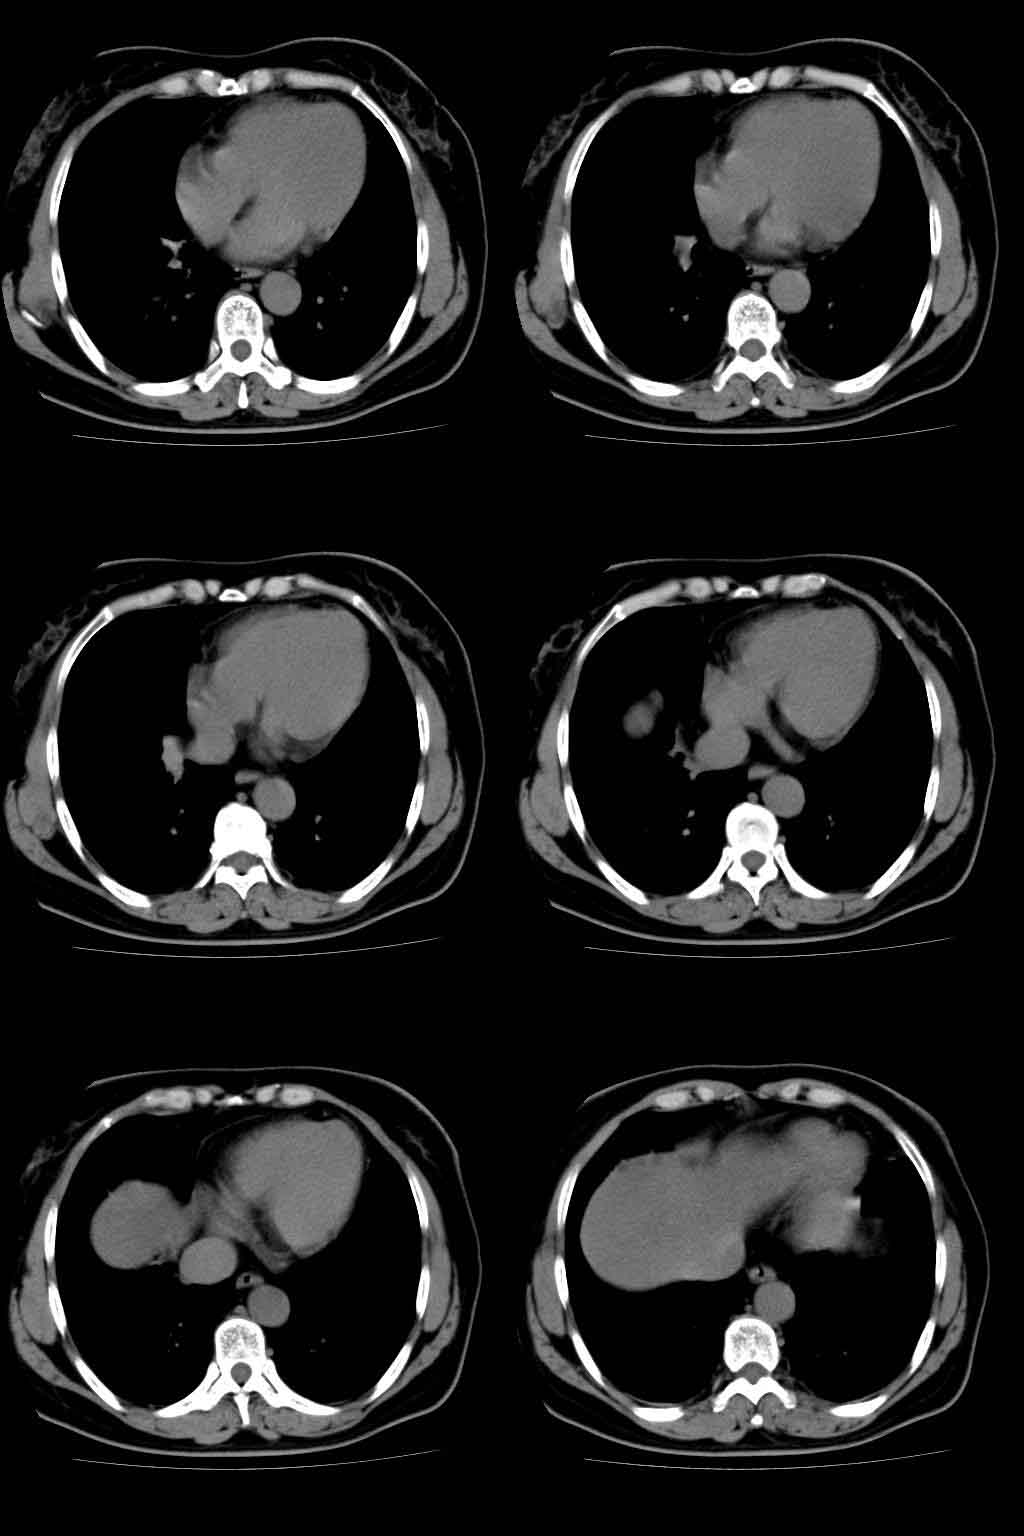

以下是引用lkc8963在2008-10-4 22:24:00的发言:[br]右下肺内基底段不规则软组织结块,肿瘤可能,建议增强鉴别于血管.